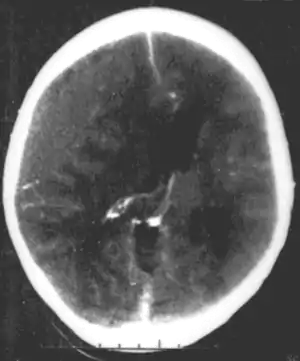

Systemic infections can result in neurodevelopmental consequences, when they occur in infancy and childhood of humans, but would not be called a primary neurodevelopmental disorder. For example HIV[27] Infections of the head and brain, like brain abscesses, meningitis or encephalitis have a high risk of causing neurodevelopmental problems and eventually a disorder. For example, measles can progress to subacute sclerosing panencephalitis.

A number of infectious diseases can be transmitted congenitally (either before or at birth), and can cause serious neurodevelopmental problems, as for example the viruses HSV, CMV, rubella (congenital rubella syndrome), Zika virus, or bacteria like Treponema pallidum in congenital syphilis, which may progress to neurosyphilis if it remains untreated. Protozoa like Plasmodium[27] or Toxoplasma which can cause congenital toxoplasmosis with multiple cysts in the brain and other organs, leading to a variety of neurological deficits.